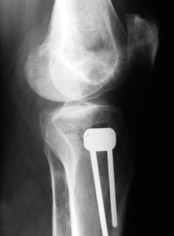

Yesterday one leg was done (my plan to make both in one session were cancelled because of external reasons). So much exciting and useful experience.

The osteotomy line i planned to make a bit oblique, but not so as you suggested. But at the moment of osteoclasis after corticotomy through the anterior stab wound the line became almost as you described. Now problem is how to reproduce thee line at the next leg ;-)

The prominent fragment seems to be useful for cosmetic purposes, because aesthetic guys perform medialization of the distal fragment to gain attractive curve at the medial side of the leg. Also all locking options became available - initially i planned to engage only two most

proximal 45 degree holes.

I cut the fibula because i externally rotated the distal fragment by 6-7 degrees. With only angular correction it didn't show any displacement.

Today CT for estimation of rotation was performed, results i will see only tomorrow. Rotation of the operated limb can be corrected with the second surgery. Comments/critics are welcome.

THX to all people discussed the case.

Yesterday i performed correction of one leg (the plan to make both in one session was cancelled because of some external reasons). Suggestions of Nuno Lopes were most close to my view. A small wire distractor was used intraoperatively. Derotation ~6-7 degrees was performed also. CT scans evaluating rotation will be available only

tomorrow. No problem to change rotation of the operated limb in the moment of the second surgery. Comments/critics are welcome.

Can the attached result be analyzed by the software?

См. снимки. Пока очевидно, что анатомическая ось большеберцовой кости заняла положение под прямым углом к проксимальной суставной площадке. Что можно расценить как 2-3 градуса гипервальгуса. А можно и считать в пределах нормы (85-90 градусов)...

АЕ> И где после операции располагается надколенник?

Где и был. Остеотомия подбугорковая.

Снимки в приложении - фас сравнительный с неоперированной ногой. Жду критики.

Впрос про остеотомию большеберцовой непраздный. Эта получилась при надломе несколько более наклонно, чем я делал (сейчас проблема,

как на второй ноге сделать так же). Вот этот высоящий "зуб" центрального отломка не заменит ли в плане косметики то, что получается при медиализации дистального?

|